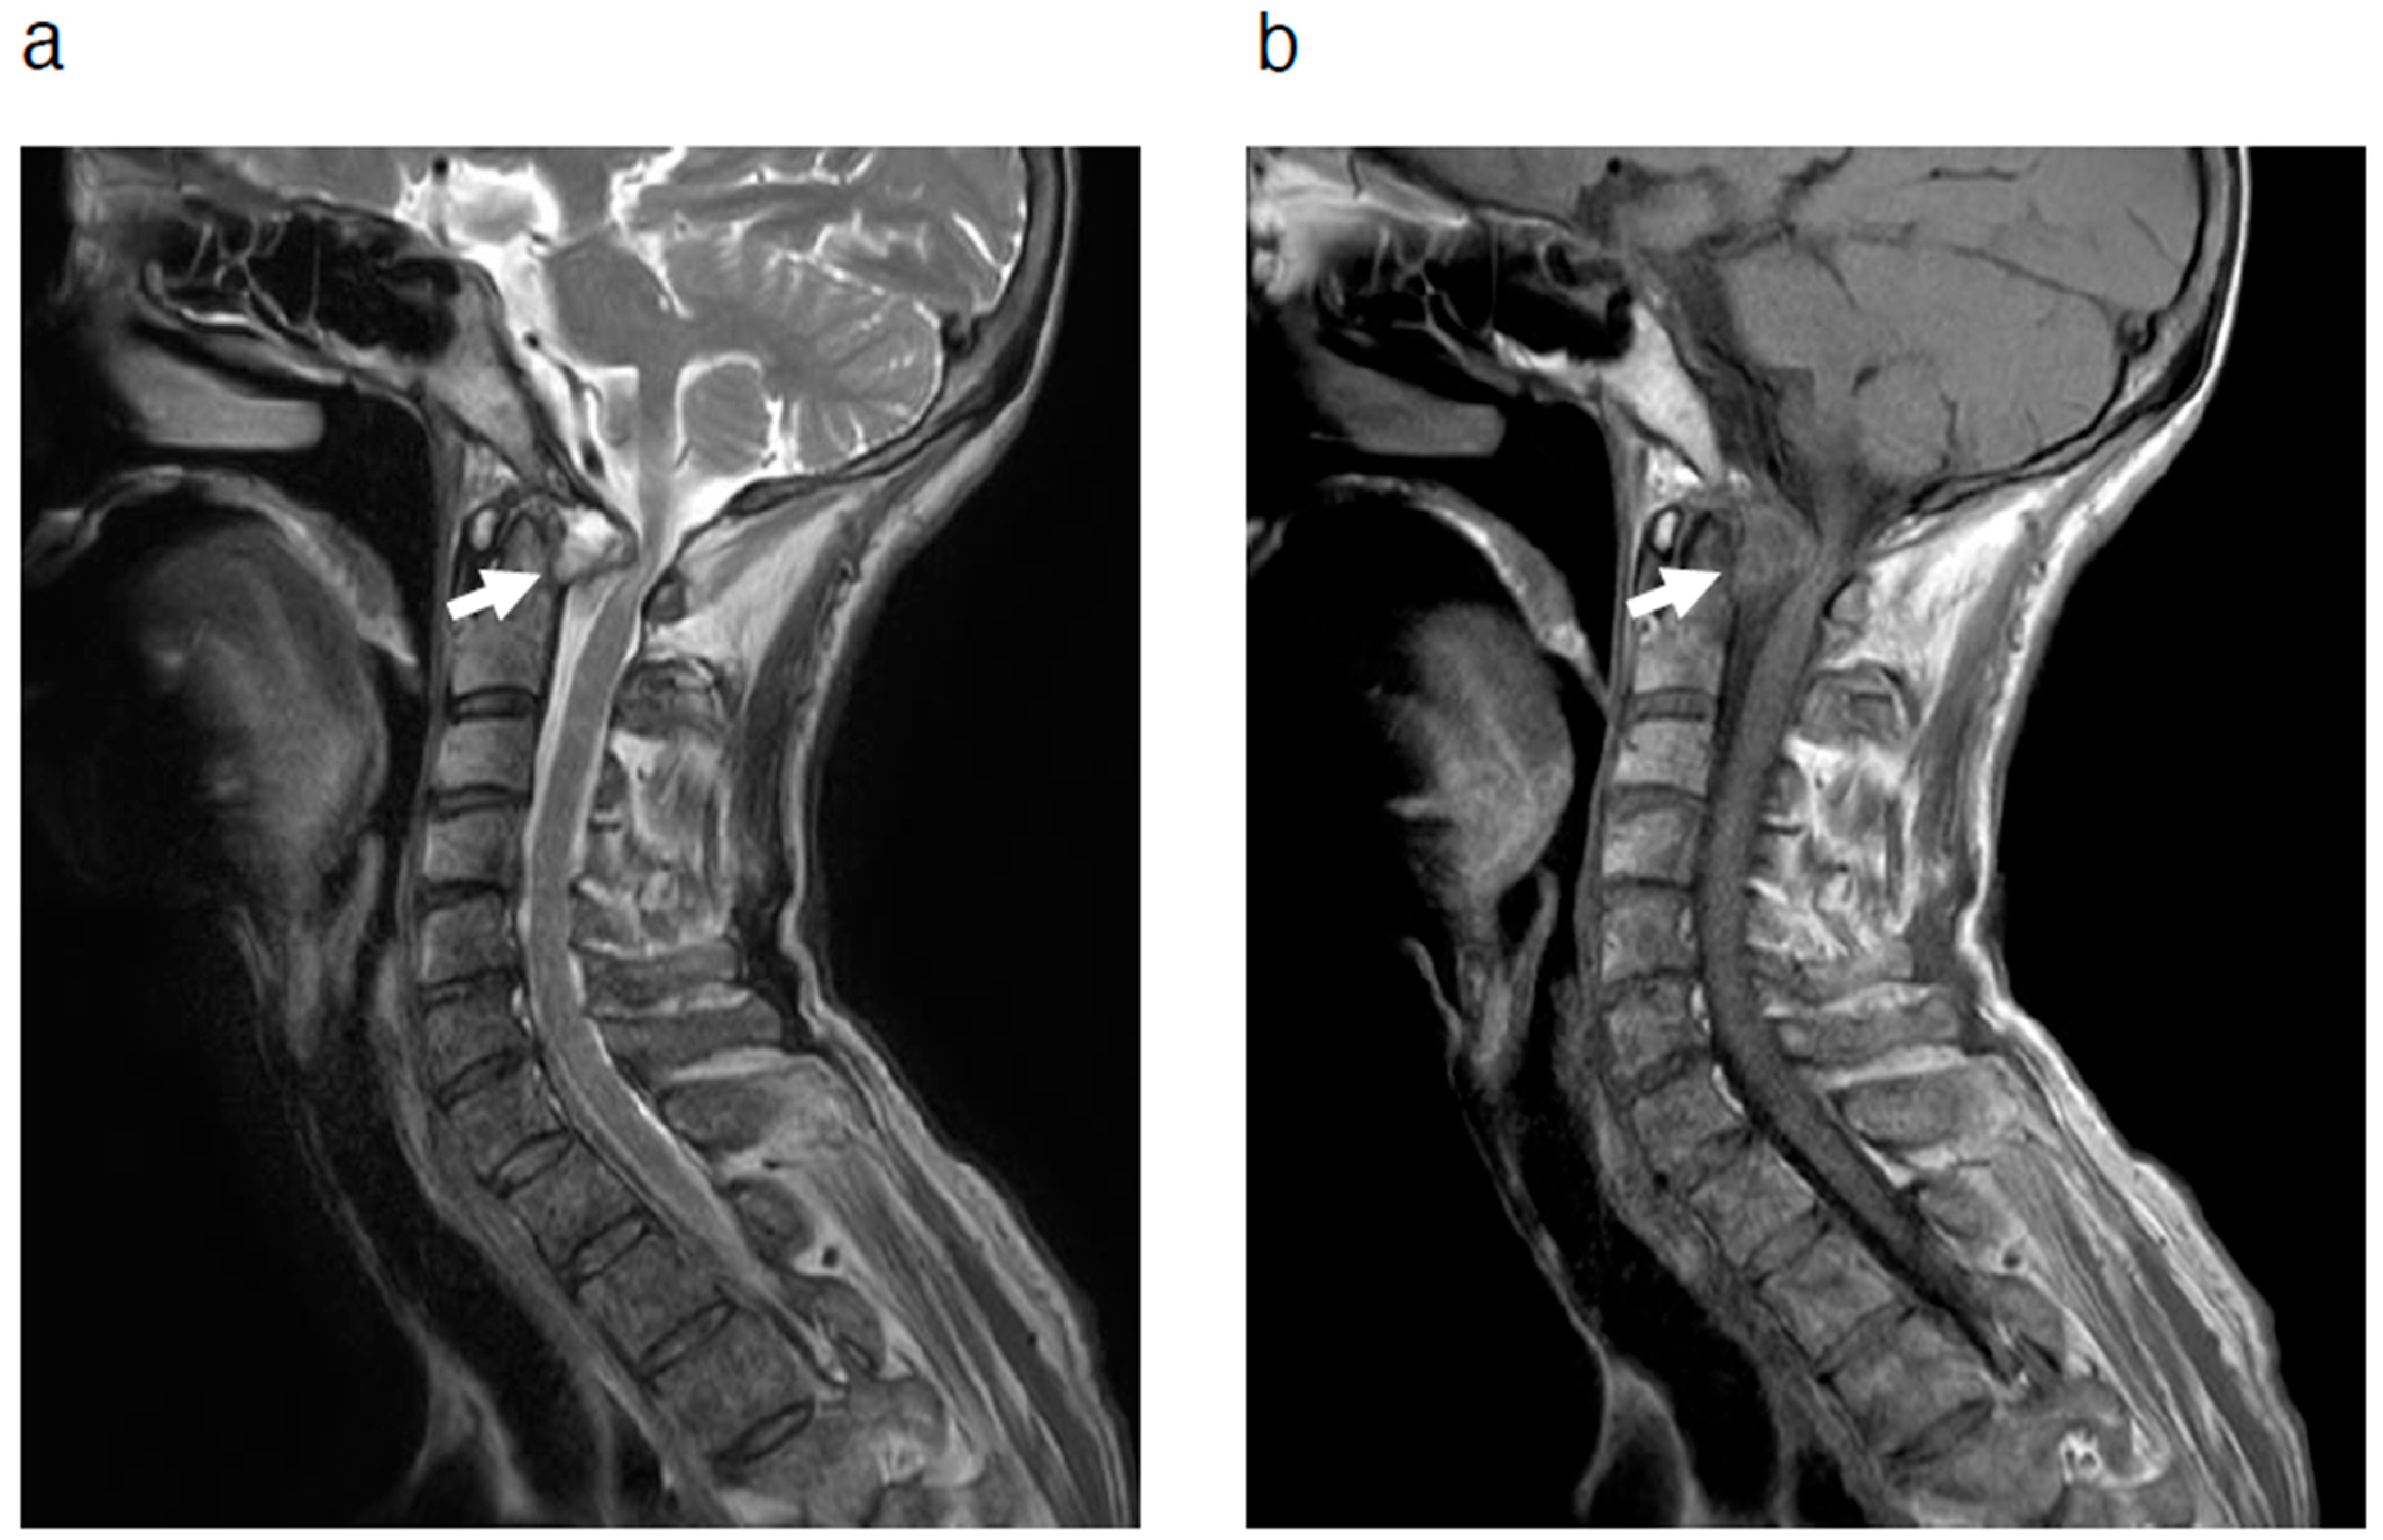

2. Case Presentation